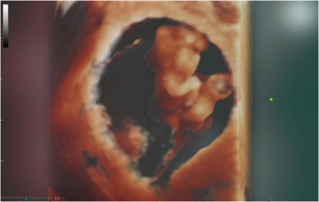

Female pelvic floor anatomy, which developed since the early 20th century, has had a variety of theories, including integral theory, three levels of vaginal support theory, "hammock hypothesis", and three-chamber system. Supporting structures such as pelvic floor muscles, fascia and ligament play an important role in maintaining the normal function of pelvic floor, among which levator ani muscle group is one of the most important supporting structures.